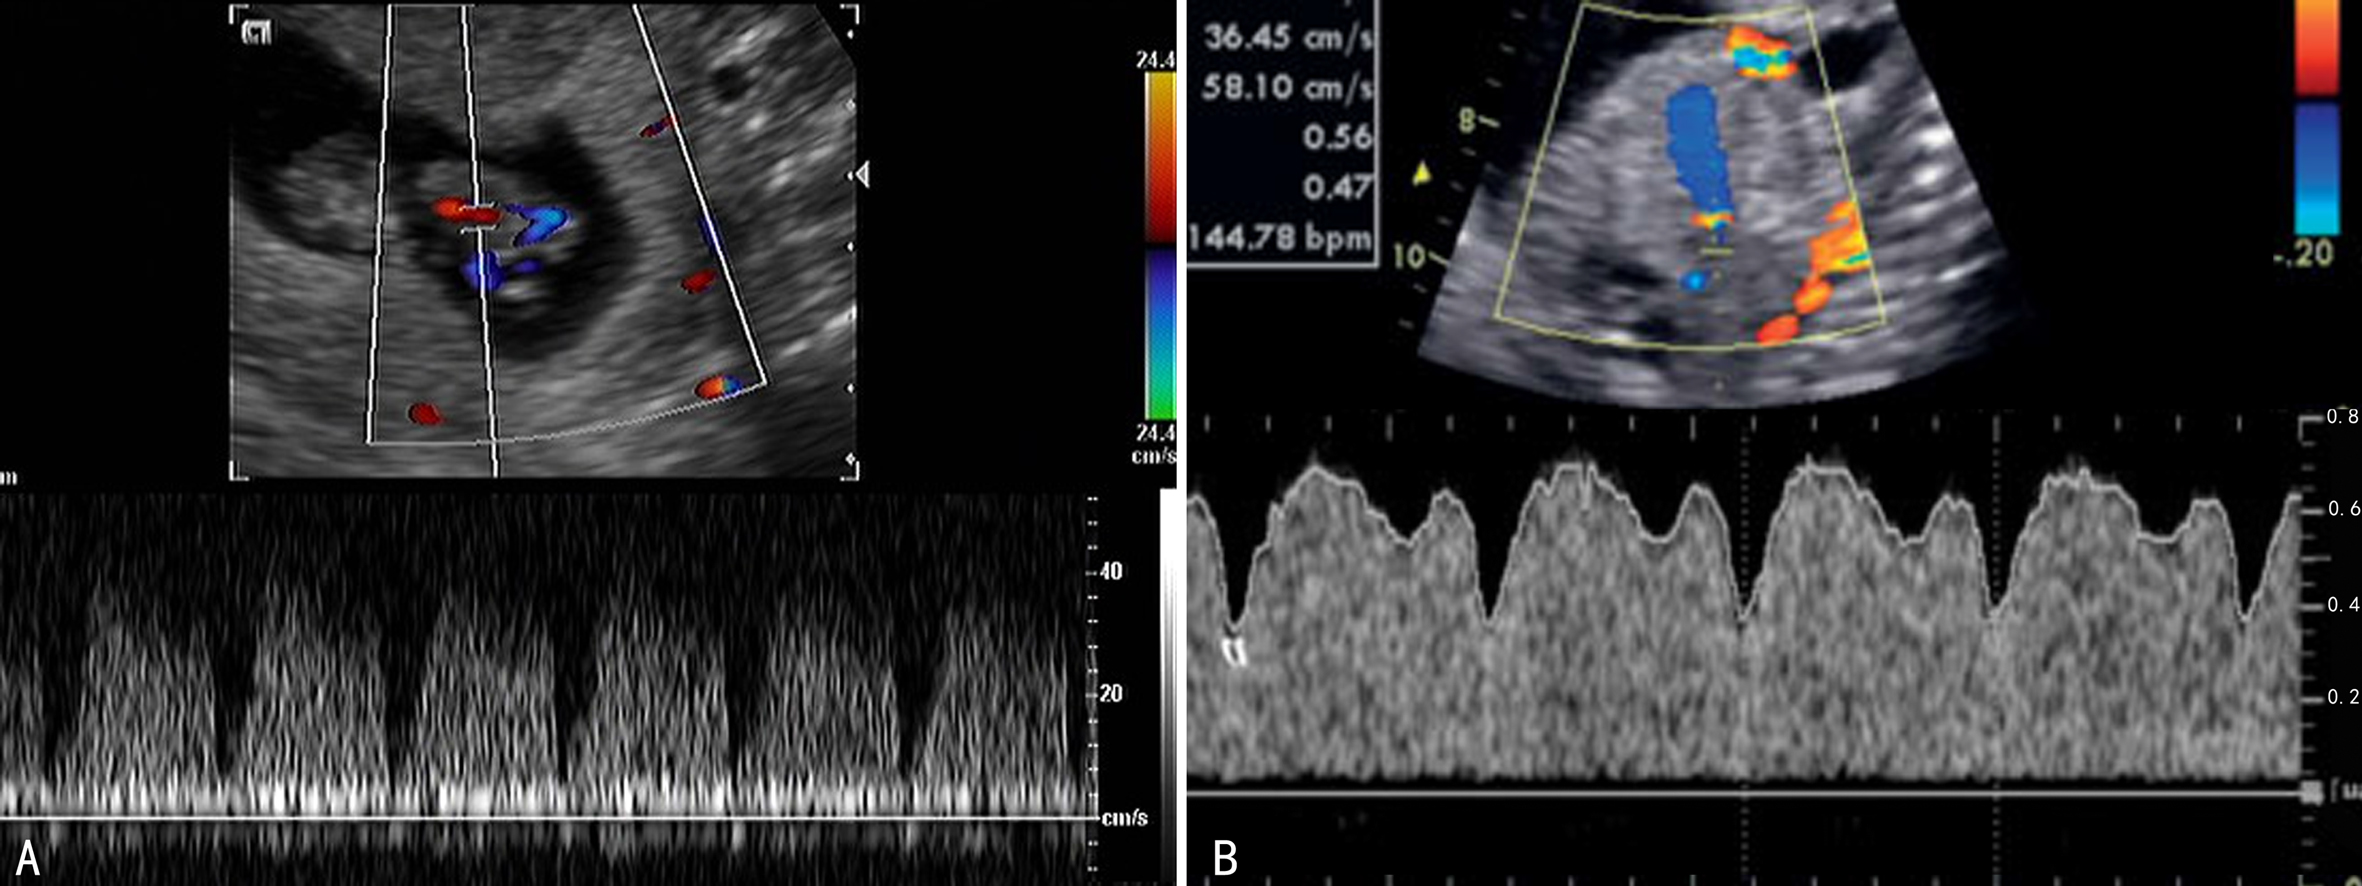

(一)降主动脉及腹主动脉

降主动脉检查的标志点位于主动脉弓动脉导管汇入处以下至膈肌动脉裂孔处。孕11周以前降主动脉无舒张期血流,显示为单峰血流,15周后出现舒张期血流,20周时舒张期血流明显增加,PI下降。FGR时降主动脉血流峰值速度降低,降主动脉舒张期血流消失。腹主动脉的显示、检测部位及血流速度曲线与降主动脉相似。

(二)肾动脉

冠状面扫查在腹部可以显示的第一对血管即为肾脏血管,于肾门处取样可以获得肾动脉血流频谱。正常肾动脉血流显示为低阻力型频谱,血流速度随孕周增加而增加,阻力指数随孕周增加而下降。胎儿缺氧时肾动脉血流阻力明显升高。

(三)腔静脉

包括上腔静脉和下腔静脉。检查可以在胎儿右心房后方显示方向相反的向心的血流,频谱多普勒检查时取样点以近右心房入口为标志点。正常上腔静脉和下腔静脉内血流频谱相似,均显示为三相波,首先是右心房收缩所致的反向A峰,其后是由右心脏收缩期引起的向心性V峰和心脏舒张早期向心性E峰。下腔静脉压力升高时可引起V/E比值减少。